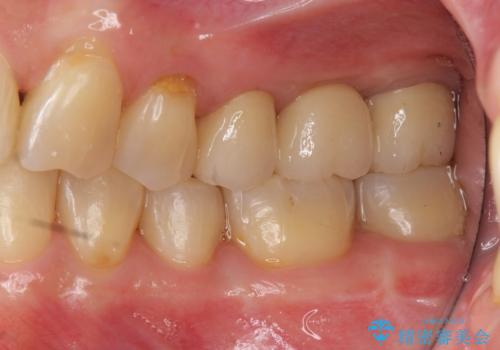

奥歯も少なく、左上奥歯はブリッジにすることになりました。

左下の前歯を中に入れるスペースを確保する目的で左下の奥歯を後ろ移動させました。

- 140.8万円(矯正治療:104.5万円、奥歯ブリッジ:36.3万円[ジルコニアクラウン10万円x3 仮歯x1万円x3])費用は治療当時の料金となります